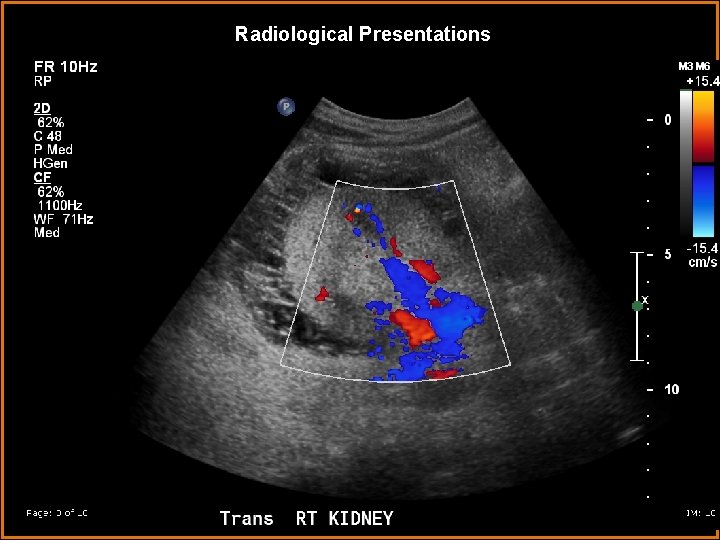

Findings and Differentials Findings: - Bilaterally symmetric hypoechoic perirenal areas, paralleling the renal contour - Multiple septations - Avascular Differentials: • Perirenal Abscess • Perirenal Effusions • Hypoechoic perirenal fat • Perirenal Hematomas

Discussion Ultrasound of the kidneys demonstrate bilateral avascular hypoechoic areas with multiple septations, these do not cause mass effect on the kidneys.